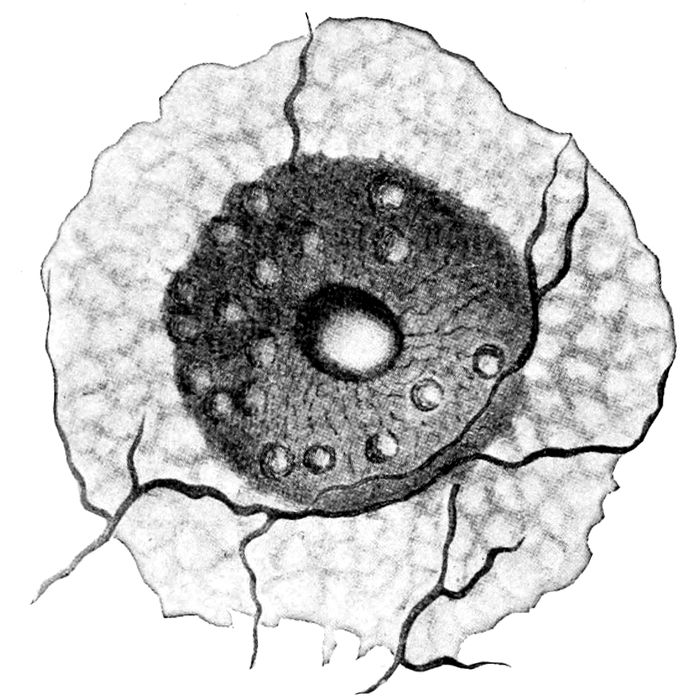

Fig. 9.—Nipple, areola, and the glands of Montgomery. (Eden.)

The nipple is pink or darkly pigmented. It is composed

into the mouth.

Surrounding the nipple is a darkly pigmented area

from one inch to four inches in diameter that is called

the areola. It contains hard, shot-like nodules, the

glands, or tubercles, of Montgomery. These often secrete

milk and sometimes become infected. It occasionally happens